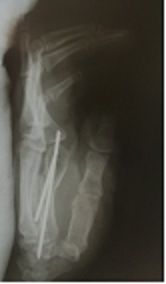

Though we manage primary healthcare, we tend to pay more focus on minor orthopedic management for adult hand surgery, including percutaneous metacarpal fracture management.

Minor orthopedic managements include: immobilization of the upper and lower limbs, closed reductions for fractures of the upper limbs, invasive and non invasive management of fractures of the hand, excisions of small subcutaneous masses of the palm, forearms and fingers as well as tendon releases.